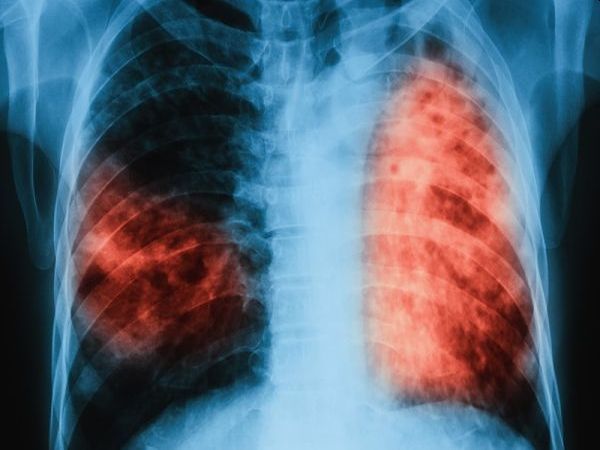

На 24 март отбелязваме Световния ден за борба с туберкулозата – заболяване, което продължава да бъде заплаха за общественото здраве, въпреки напредъка в медицината, припомнят от Министерството на здравеопазването.

Туберкулозата е инфекциозно заболяване, което се предава по въздушно-капков път и може да засегне всеки. Разпространението ѝ е пряко свързано с имунизационния обхват, ранното откриване и навременното започване на лечение.

Ранната диагноза и последователното лечение са от решаващо значение – както за здравето на пациента, така и за ограничаване на разпространението на инфекцията.